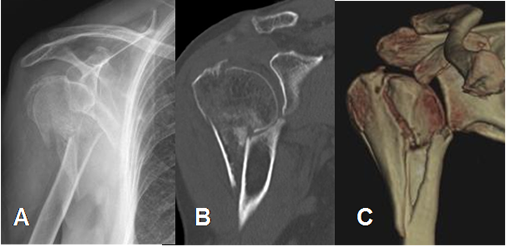

La principal indicación para realizar tomografía axial computarizada (TAC), es el trauma. Las reconstrucciones 3 D de fracturas en la cabeza del húmero, son de mucha utilidad para planear la reconstrucción quirúrgica. (12). (Fig 11).

Fig 11. TAC reconstrucción 3D.

A: Rx AP de hombro y B: TAC reconstrucción coronal. Fractura conminuta y desplazada del

cuello humeral.

C: TAC reconstrucción 3D. Se confirman los hallazgos y permite valorar las relaciones articulares.